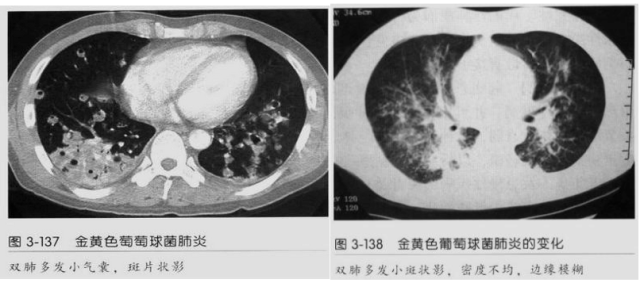

4.容易在短期内出现散在的肺气囊或多发的脓肿病灶;

5.病灶易变,短期内复查CT可见病灶的形态、部位、大小发生变化。

3.空洞:分为两类。

第一类,偏心空洞,一侧壁厚,周围实变明显。

第二类,薄壁空洞(偏中后期):壁薄且均匀,内外壁光滑,张力高,内有气液平面、间隔影,各空洞相对独立互不相通

4.囊:张力高,壁薄,内外壁光滑,可有间隔

5.边缘收缩明显,结节密实,边缘收缩、凹陷,周围长索条影,提示吸收好转

6.胸腔积液、脓胸